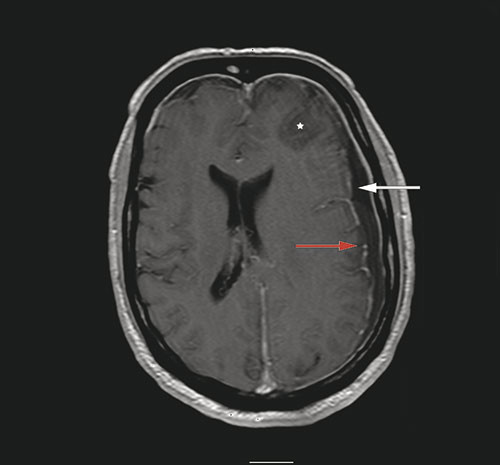

A man in his sixties was admitted to a local hospital after he was found confused and with impaired consciousness. According to informants, he had by then suffered headache for two days. On examination, he had high fever (40.5 °C), neck stiffness and a Glasgow Coma Scale score of 12. The neurological examination was otherwise unremarkable. Cerebral CT with bone window in the sagittal plane (image on the left) showed opacification of the frontal sinus and a bony defect (arrow) into the epidural space. T1-weighted contrast MRI (image on the right) showed a left-sided subdural effusion (white arrow), contrast enhancement of the dura (red arrow) and signal changes (star) in the left frontal lobe. His cerebrospinal fluid appeared turbid with a white blood cell count of 2187 · 10⁶/l (normal 0 – 5) and total protein of 1.55 g/l (normal 0.15 – 0.50). On suspicion of subdural empyema and cerebritis, the patient was provided with antibiotic therapy and transferred to the university hospital. There he underwent craniotomy and evacuation of the empyema as well as sealing of the defect in the frontal bone. Culture of the empyema revealed Streptococcus intermedius (Milleri).

Subdural empyema often presents with high fever, headache and impaired consciousness and may cause focal neurological deficits and seizures. It can be caused by the spread of bacterial sinusitis through erosion of bone barriers to the epidural space (1). Cerebral MRI enables visualisation of cerebral infections with a high degree of sensitivity (2) and it is essential that patients with a demonstrated empyema or abscess are promptly referred for surgical drainage (1).